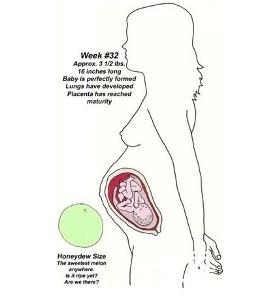

8.32周末

胎儿身长约40厘米,体重约1700克。皮肤深红,面部毳毛已脱,生活力尚可,出生后加强护理可能存活。

第三十二周:32周的胎儿身长约45厘米,体重约2000克。如果宝宝是男孩,他的睾丸可能已经从腹腔进入阴囊,但是有的宝宝可能会在出生后当天才进入阴囊。